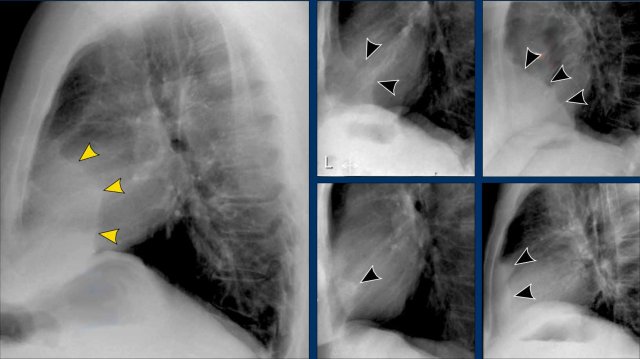

Spondylosis Mimicking Lung Lesions

Degenerative changes of the spine (spondylosis) can occasionally simulate a pulmonary mass on the lateral view.

• Any opacity in the region of the vertebral bodies should prompt correlation with the PA view to assess for spondylotic osteophytes, which are typically located on the right side.

• On the left, osteophyte formation is less pronounced due to aortic pulsations that inhibit calcification.